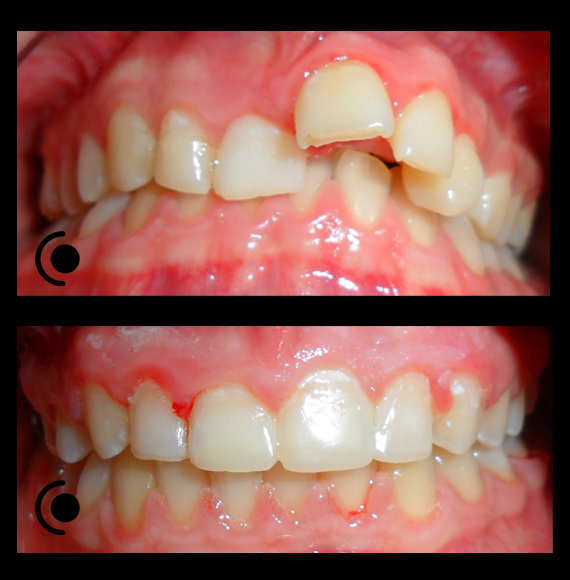

O našoj kvaliteti najbolje govore naši rezultati!

Centar za ortodonciju Petra Džapo